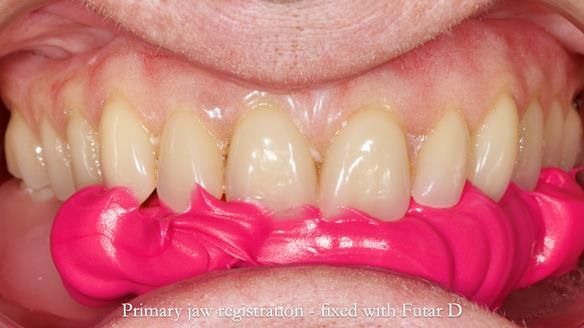

- Upper working impressions were border-moulded with greenstick compound along the sulcus borders and made in alginate.

- The gasket seal around 46 was made using retention.sil 200, producing a precise, cushioned fit.